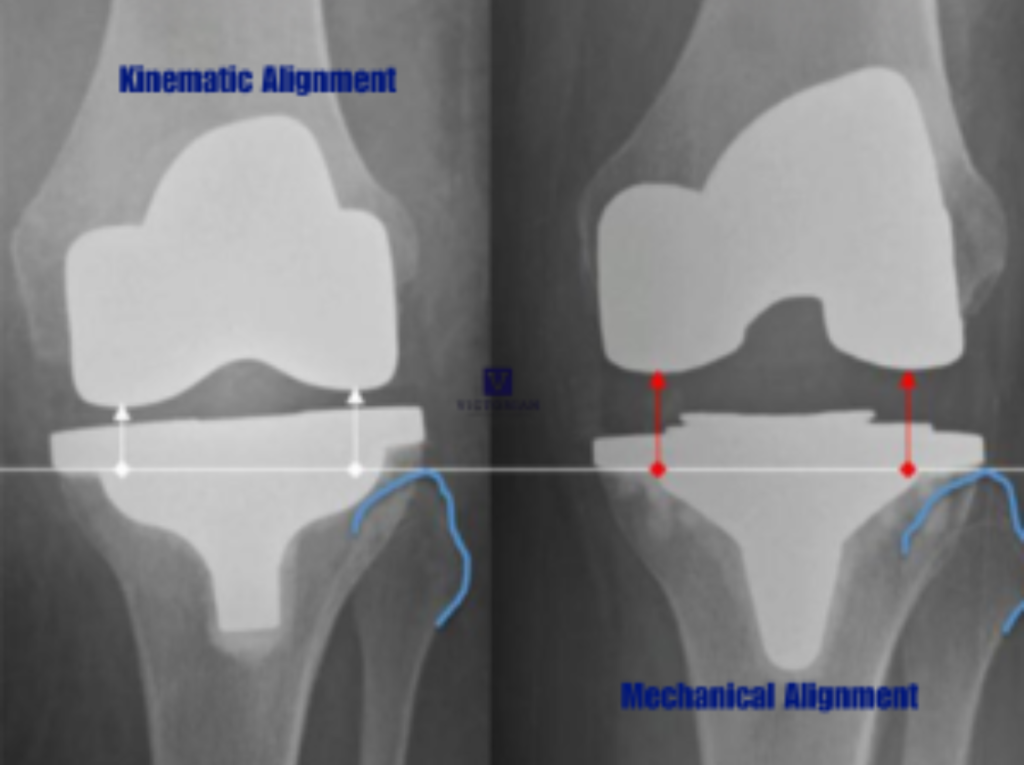

Kinematically Aligned Total Knee Replacement